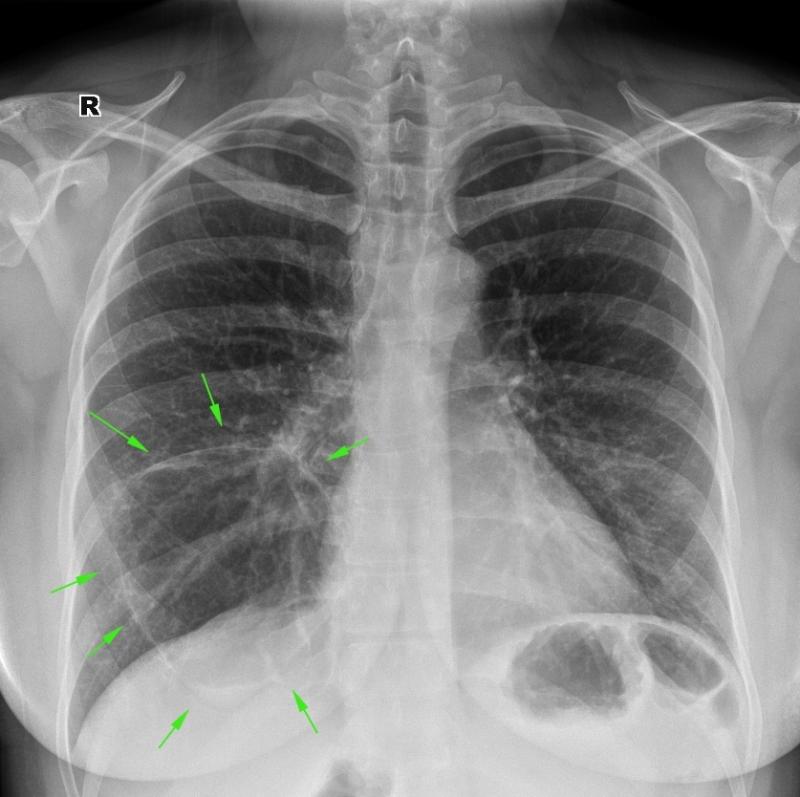

Медицинская тема: легочные осложнения при пневмонии